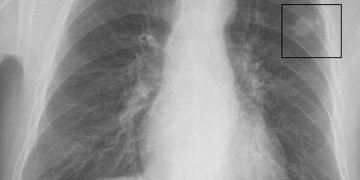

حقيقة صادمة كشف عنها المعهد القومي للأورام حول سرطان الرئة الذي تسبَّب في وفاة الفنان هشام سليم.

وأضافت خلال مداخلة هاتفية مع إحدى الفضائيات ” إن سرطان الرئة أصبح ترتيبه الثالث بين أكثر أنواع السرطانات انتشاراً بعدما كان ترتيبه الخامس، مشيرةً إلى أنه ينتشر حالياً في سن أصغر، ويتوقع تزايده خلال السنوات المقبلة.”

وحذررت من أن أزمة المرض تكمن أن اكتشافه يكون في مراحل متأخرة من المرض، إذ إن 80% من الحالات تكتشف إصابته به في مراحل متأخرة منه مشكلة المرض الكبرى تكمن في المرحلة الرابعة والتى يكون الشفاء فيها صعباً جداً».